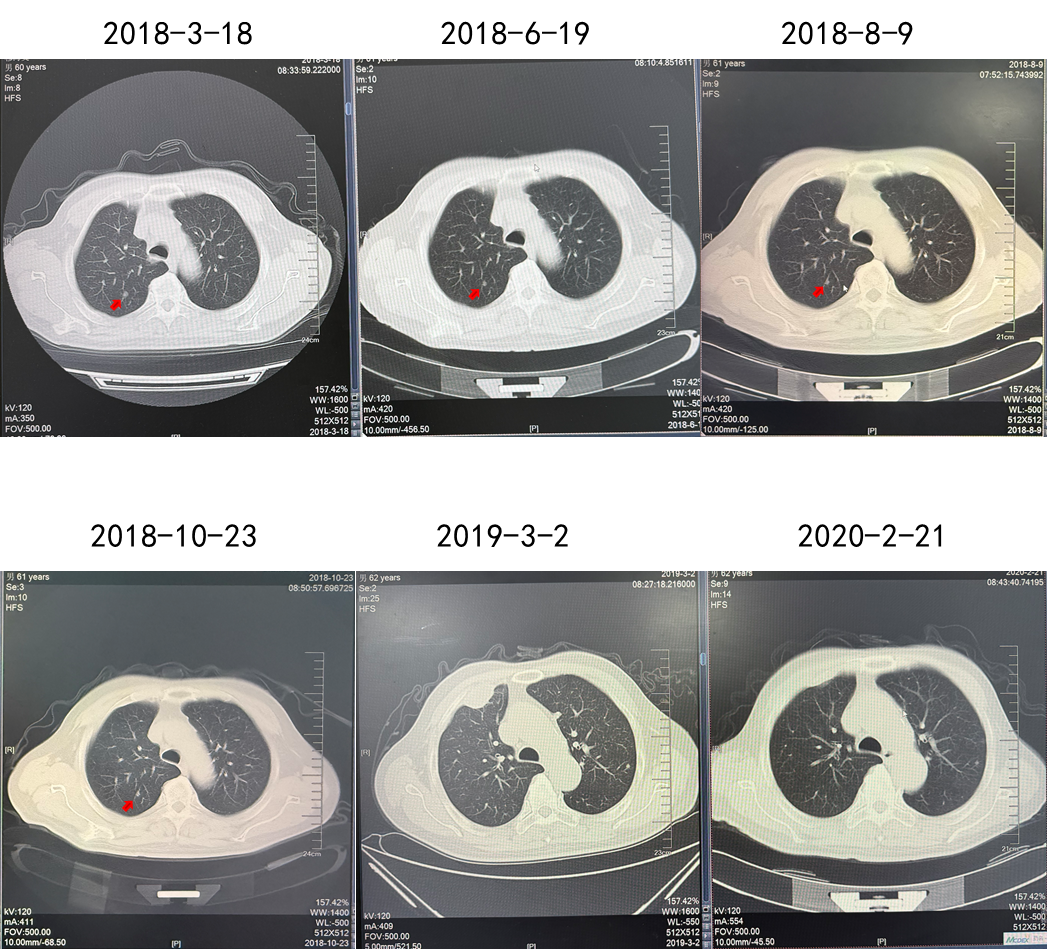

疗效:肋骨病灶疾病稳定(2年),肺部病灶部分缓解(2年)。

(舒尼替尼单药联合放疗,肋骨病灶实现SD)

(舒尼替尼单药联合放疗,肺转移病灶实现PR)